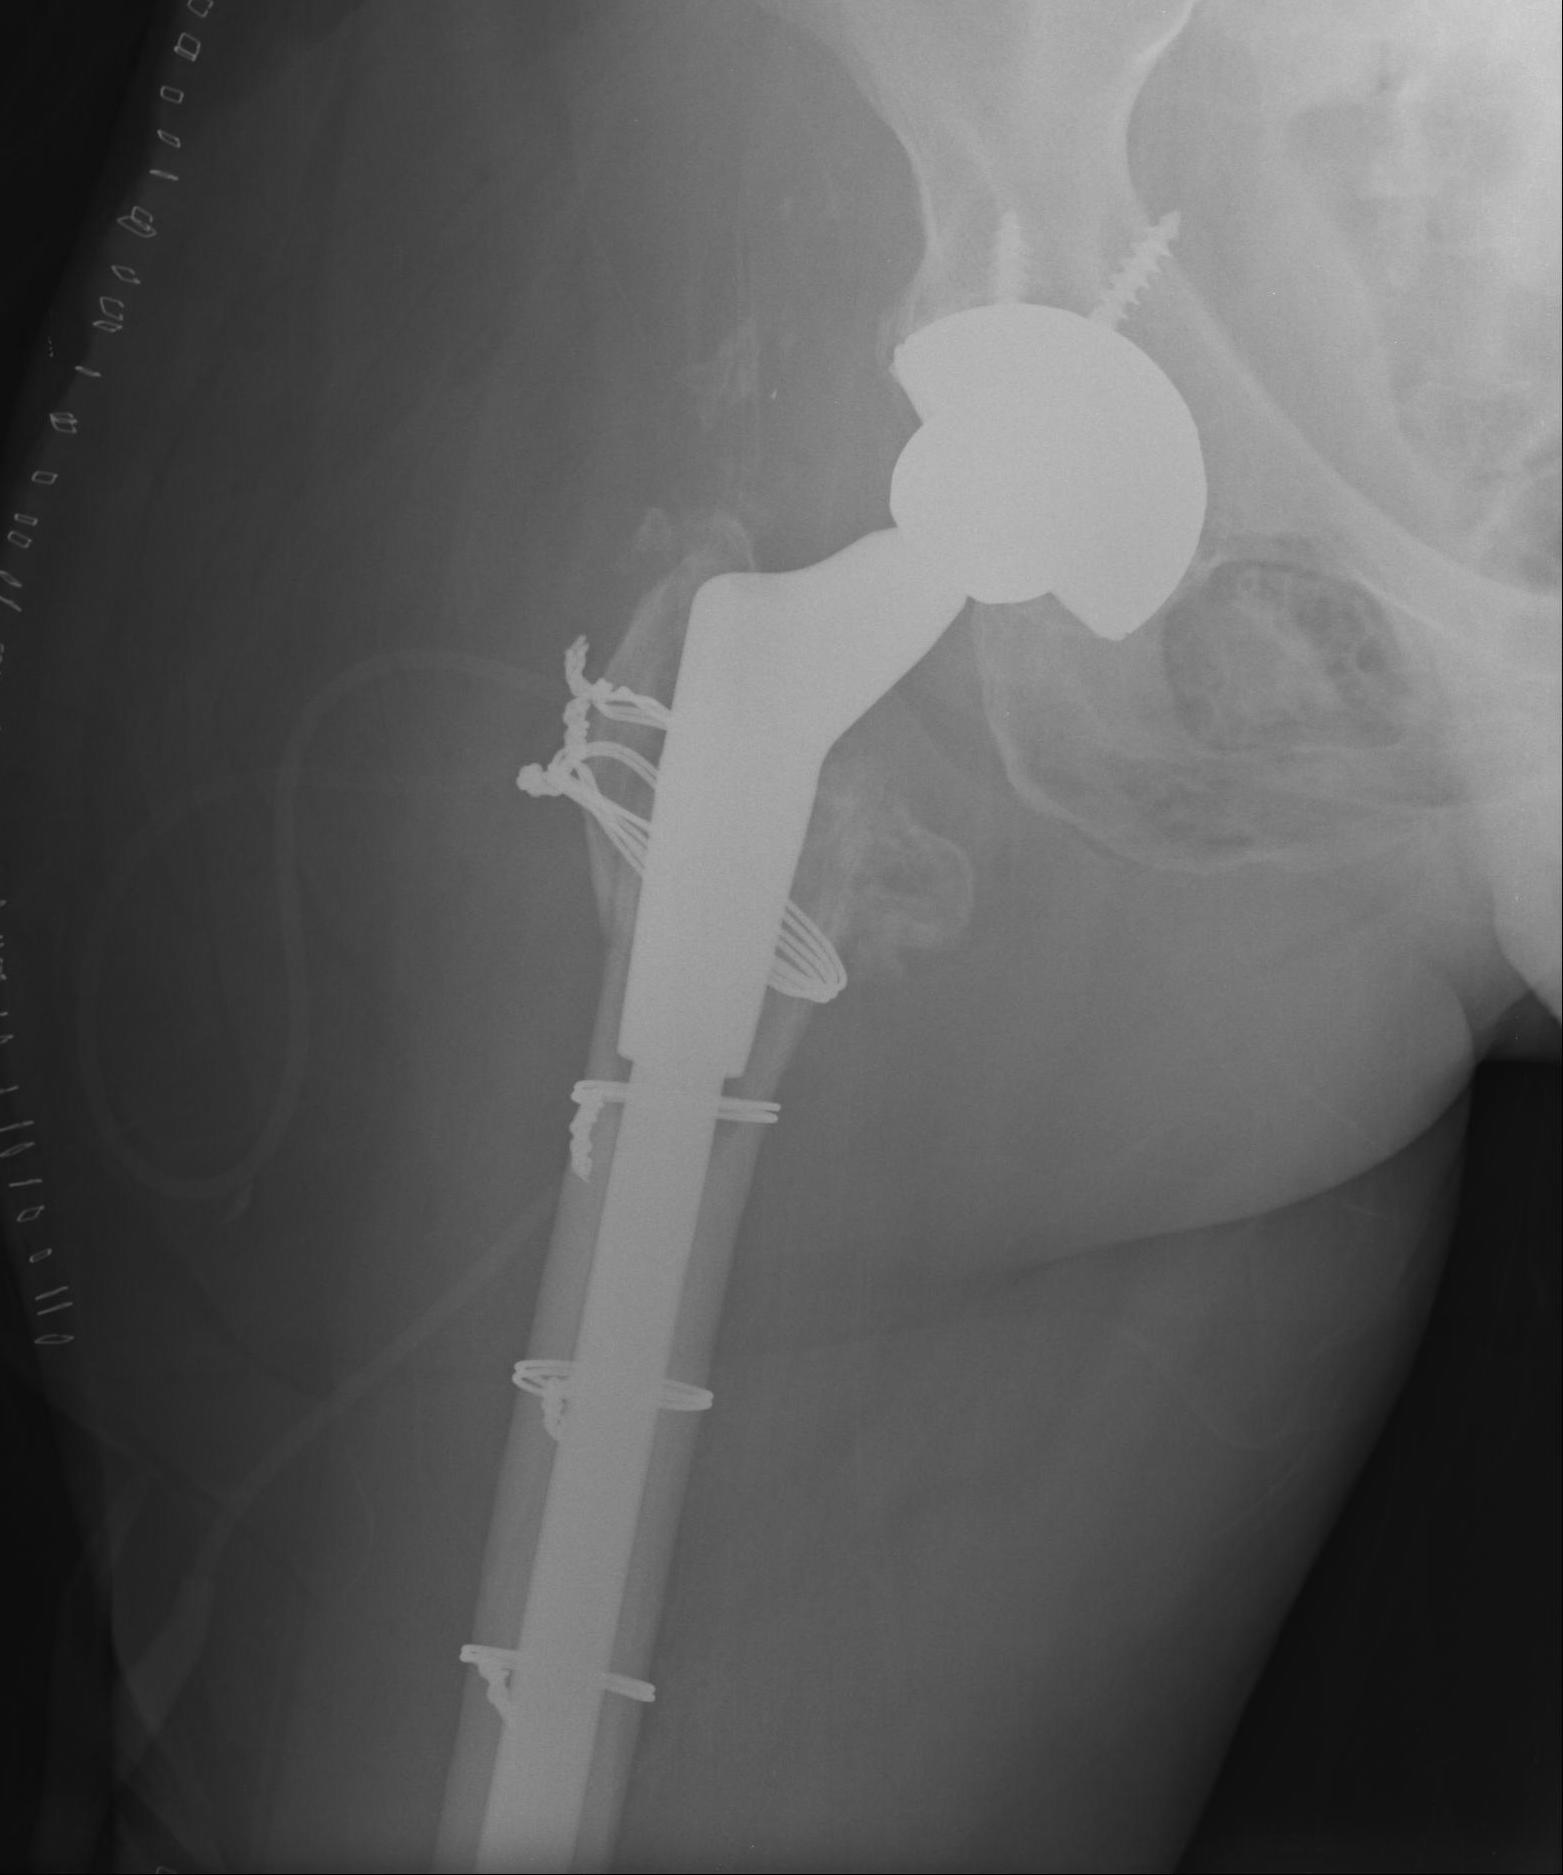

2. Extensively porous coated diaphyseal fitting uncemented stem

Indications

- Paprosky Types I, II, IIIA

Results

- 90- 95% 10 year survival

Problems

- fracture

- stress shielding with additional proximal bone loss